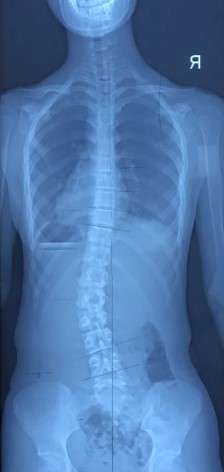

以最常见的腰椎左侧弯为例(图 1)。

患者自然坐位下的外观跟X光片是相符的,左侧腰切迹较突出,右侧腰切迹较凹陷(图 2)。

我们可以让患者在左臀下垫一本书,被动抬高左髋。左髋的抬高会被动地将腰椎推向右侧,使脊柱处于中立位或过矫正的位置(图 3)。

书的高度靠自我感觉和腰切迹的对称性来判断。书垫得越高,过矫正的就越多;但书垫得越高,患者就会越不舒服,可持续性就会越差。所以,书的高度只需要垫到两侧腰切迹对称或右侧稍稍有一点点过矫正,而且本人的感觉是舒服的,可以一直维持下去的状态就可以了。腰椎右侧凸的患者,同样的思路垫右臀即可。